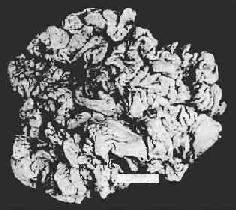

图10-4 胃粘膜肠上皮化生 胃粘膜上皮出现多量充满粘液的杯状细胞 3.肥厚性胃炎(hypertrophic gastritis) 又称肥厚性胃病(hypertrophic gastropathy)、Menetrier病。发病原因不明。病变特点是,粘膜肥厚,皱襞加深变宽似脑回状(图10-5)。镜下,腺体肥大增生,腺管延长。粘膜固有层炎性细胞浸润不显著。粘膜表面粘液分泌细胞数量增加,壁细胞及主细胞有时减少。临床上,多数患者有胃酸低下及因蛋白由胃液丧失而致的低蛋白血症。

图10-5 慢性肥厚性胃炎 胃粘膜肥厚,皱襞加深变宽似脑回状 4.疣状胃炎(gastritis verrucosa)是一种有特征性病理变化的胃炎,病变处胃粘膜发生一些大小不等的糜烂,其周围粘膜隆起,因而形成中心凹陷的病灶,形如痘疹。病灶主要分布在幽门窦部。病变活动期,镜下可见病灶中心凹陷部的胃粘膜上皮处于变性、坏死和脱落状态并伴有急性炎性渗出物覆盖病灶表面。病变修复时局部粘膜上皮再生修复。有时可见修复上皮呈不典型增生。本病与一般的单纯性胃粘膜糜烂不同,其发病机制尚有待查清。